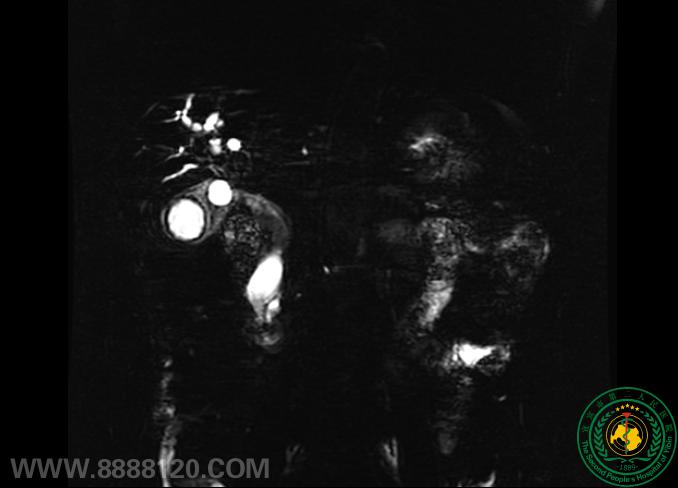

案例一:患者68岁男性,因“持续性上腹疼痛16天”入院。入院后查胰腺炎及肿瘤标志物均正常,磁共振CT均提肝内外胆管及主胰管扩张,没有发现明确占位病变超声内镜检查发现了一个大小约1.9×1.2cm的胰腺微小肿瘤。

MRCP